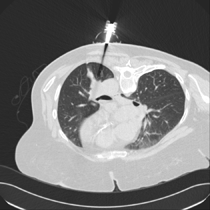

Mit einer scheinbar simplen Innovation der schwedischen Firma AprioMed hat der Arzt nun die Möglichkeit, bei einer Biopsie am CT schon vor dem Einstich den Nadelpfad zu erkennen und gegebenenfalls zu korrigieren. Bisherige Lösungen haben unter anderem auf Laserunterstützung gesetzt. AprioMed will diese kostenintensiven Produkte durch die Eigenentwicklung SeeStar® ersetzen.

Die schwedische Firma AprioMed AB aus Uppsala produziert und entwickelt Zubehör für Radiologen. Für Biopsien am CT hat man die Einführhilfe SeeStar® entwickelt, damit der Arzt eine schnelle und günstige Möglichkeit hat, vor der Biopsie den Einstichwinkel zu bestimmen und während der Biopsie einen gleichbleibenden Zugang zu behalten.